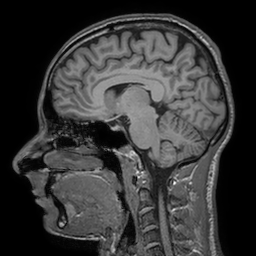

In [152], a variant of the adaptive weights smoothing employing a statistical penalty as the maximum over a local (rectangular) patch of voxels was defined. This patchwise adaptive smoothing combines the iterative procedure outlined above with the idea of patchwise comparisons used by non-local means (NLM) [29]. The resulting procedure combines the edge preserving property of the original method while avoiding the cartoon-like appearance of the reconstructed image that is the result of the structural assumption above. In [152] the method was extensively compared with TV and TGV based reconstruction methods, see the Figure 6 and 7 within this paper. In Figure 5, we provide an example reconstruction of a noisy MR image (from fully sampled k-space), where weighted example data has been taken from the IXI Dataset [111].